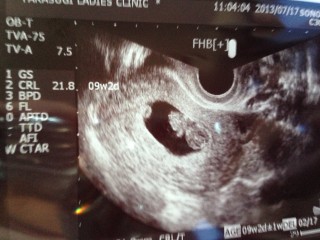

CRLは21.8mm(^ ^)

元気だよ!と言われ、ほっとしました。 9W2D、21.6mmでした。 2週間ぶりの検診だったのですが、ドキドキだったのですが元気で良かった☆ 母子手帳をもらうための書類もこの日にもらえました。